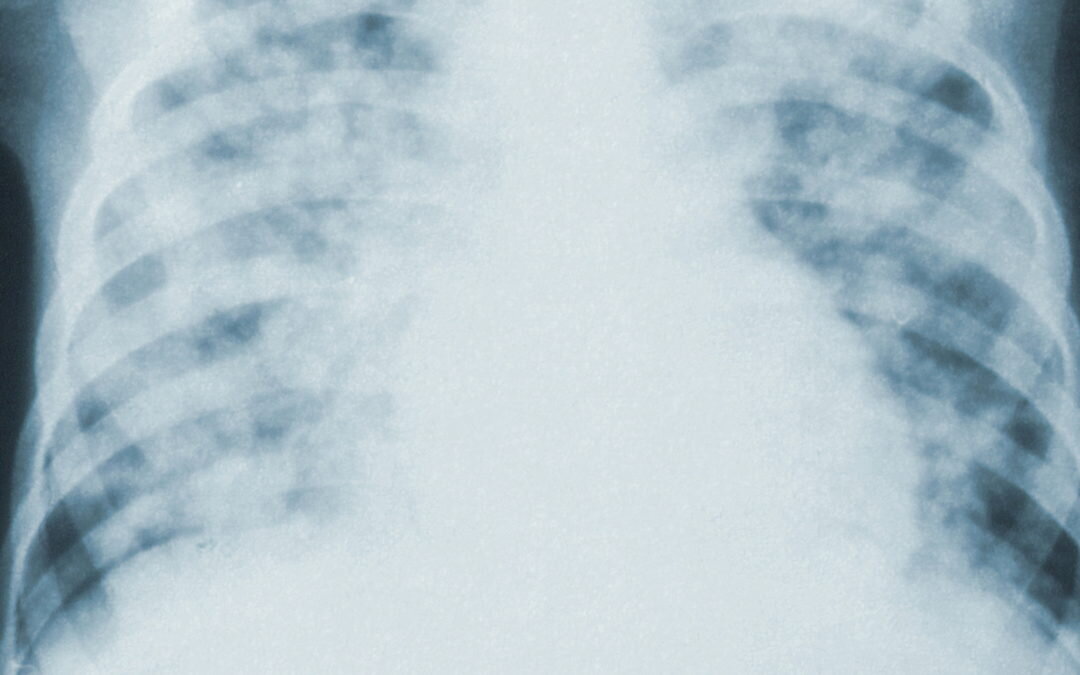

фото из La Tribune